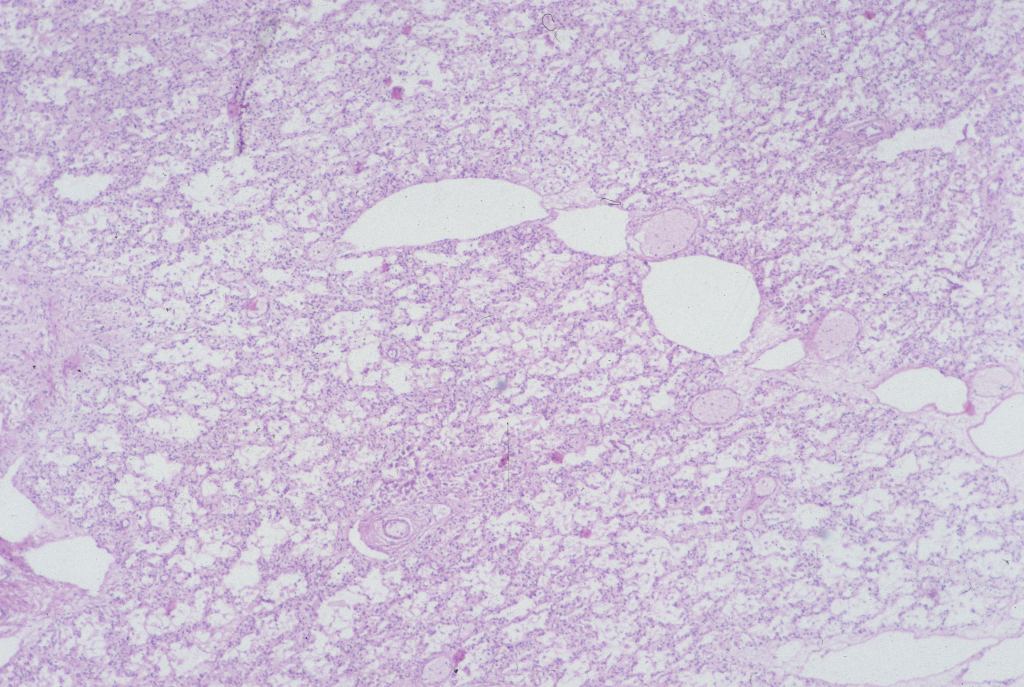

Distal airway expansion: The lung in the fetus is naturally in the unexpanded state. With respiratory effort, even in fluid, there may be some expansion of the air passage. A complicating postmortem event is focal expansion of airways with gas (Fig 25).

This gas is presumed to be from bacterial action in the lung, usually with no evidence of inflammation. The importance of this phenomenon is that it not be mistaken for postnatal respiration in a stillborn fetus not born in the hospital with the forensic inference that respiration had occurred and death was after delivery.